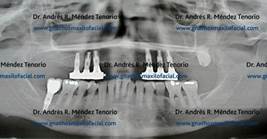

| Rx panorámica donde se observa resto radicular de premolar superior derecho junto a una lesión periapical del premolar adyacente | |